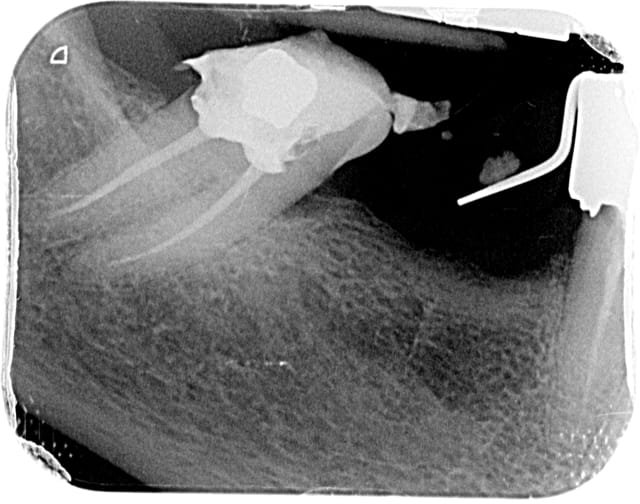

un patient adressé pour endo 47 ou j'ai utilisé les pathfiles puis mise en forme classique

Dardenne 1 oavcsl - Eugenol

Dardenne 2 nz16af - Eugenol

Sur mon cas clinique en mésial la lime 8 manuelle n arrivait qu à mi racine et avec la pathfile équivalente ça m a permis de très vite . progresser. ..

J essaye toujours avec une lime manuelle pour explorer l anatomie de la dent.

mais dans certains ces limes sont vraiment un très gros coup de pouce...